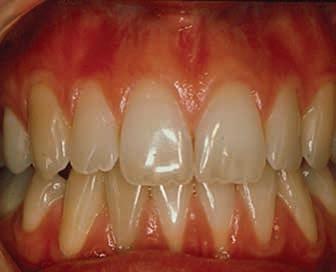

Lichen planus presents in various forms in the mouth including reticular, plaquelike, papular, atrophic, ulcerative, and bullous forms. Lesions range from asymptomatic, white lacy lines (Wickham’s Striae) in the reticular form and dense thickening of the mucosa in the plaque-like form to erythema and ulceration in the atrophic and ulcerative forms. In the former, patients may complain of sensitivity to spicy, acidic, and rough-textured foods as well as difficulty with oral hygiene (Figures 1,2).

Figures 1 and 2. Lichen planus occurring on the gingiva (desquamative gingivitis) and tongue (plaque-like form). Figure 1 Figure 2